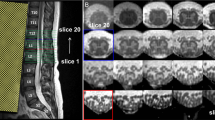

Ex vivo high-resolution spinal cord

To evaluate our method on an ex vivo dataset, we used an MRI acquisition that was performed on an entire human spinal cord41, from the pyramidal decussation to the cauda equina using a 7 T horizontal-bore small animal MRI system.

MR images of the entire spinal cord were acquired in seven separate overlapping segments. The segment field of view was 8 × 2 × 2 cm with 1 cm of overlap on each end. Between each acquisition, the specimen was advanced precisely 7 cm through the magnet bore using a custom-machined gantry insert. T2*-weighted anatomic images were acquired using a 3D gradient echo sequence with an acquisition matrix of 1600 × 400 × 400, resulting in 50 micron isotropic resolution. Scan parameters included: TR = 50 ms, TE = 9 ms, flip angle = 60°, bandwidth = 100 kHz and number of averages = 1. Per-segment acquisition time was 2 hours 22 minutes, resulting in a total acquisition time of approximately 16 hours. Individual image segments were composed into a single volume using automated image registration and weighted averaging of overlapping segments.

The volume is comprised of a total 4676 axial slices with 100 isotropic resolution.